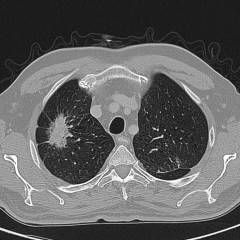

Лучевая анатомия рака легких

Лучевая диагностика рака легких имеет огромное значение в первичной диагностике. На рентгенограммах легких могут определяться тени различных размеров, форм и интенсивности. Основным признаком раковой опухоли является бугристость поверхности и лучистость контура.

В зависимости от рентгенологической картины различают следующие виды рака легких:

• центральный рак (фото А);

• периферический рак (узловатая, пневмониеподобная, плевральная, полостная формы) (фото Б);

• медиастинальный рак (фото В);

• верхушечный рак (фото Г).

4. Компьютерная томография (КТ)

Преимущества:

• Высокая информативность.

• Метод основан на выполнении тонких срезов (по типу анатомических срезов Пирогова) рентгеновскими лучами за короткое время воздействия (15-30 секунд).

• Общее время проведения самого исследования составляет 7 – 30 минут.

• Позволяет представить трехмерное измерение органов, включая сосуды, лимфатические узлы, мягкие ткани и другое.

• КТ также позволяет проводить исследования с контрастированием.

• Решение вопроса о необходимости проведения КТ принимает лечащий врач совместно с рентгенологом.

Возможности:

• выявление самой опухоли;

• дифференциальная диагностика с другими заболеваниями органов грудной клетки (такими как туберкулез, доброкачественные образования, инфекционные и паразитарные болезни органов дыхания, врожденные патологии, патологии сердечно-сосудистой системы и др.);

• точное определение размеров, положения, распространенности, вида и стадии образования.